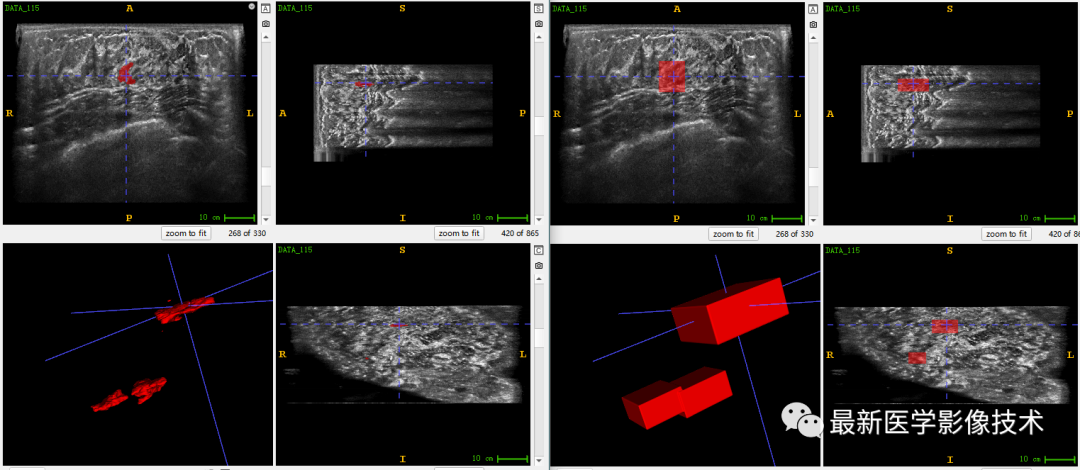

乳腺肿瘤分割采用两阶段分割网络,第一个网络进行粗分割定位肿瘤位置,第二个网络进行精分割得到肿瘤精确轮廓,然后在根据精分割mask和对应ROI图像进行良恶性分类。具体实现可以参考这篇文章TDSC-ABUS2023——2023 年自动化 3D 乳腺超声 (ABUS) 的肿瘤检测、分割和分类挑战.

验证集分割和检测部分结果如下所示。